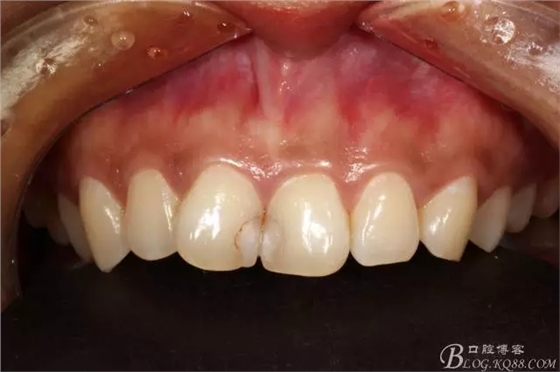

這位女患者,我第一次接診是在2012年2月,當(dāng)時(shí)25歲。

主訴:門牙中間有蛀牙,變色發(fā)要求處理。

檢查就是11、21相鄰面齲壞,

當(dāng)時(shí)患者選擇了價(jià)位比較實(shí)惠的樹脂修復(fù),3mz250樹脂充填。

2012年2月接診是的情況